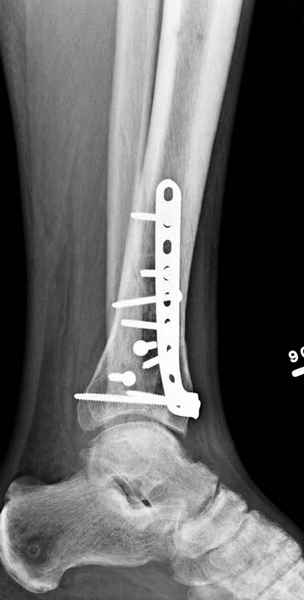

Если есть ЭОП, то перелом подходит для малоинвазивной фиксации. Репозиция суставного отдела (использовать репозиционные щипцы)и его фиксация стягивающими винтами чрезкожно, затем пластина медиально малоинвазивно, лучше метафизарная. Если не располагаете подходящим имплантом или непозволяют мягкие ткани, вполне возможно применить вместо платы Fix.Ex.

В примере показан не перелом пилона, а эпифизеолиз, м/берцовую кость сознательно не фиксировал(длина её восстановлена, ротации нет),у детей стараемся минимизировать операц.травму, несколько позже разрешил полную нагрузку на ногу(4 недели). Но принцип фиксации б/берцовой кости м.б. таким же.

Проблем с закрытой(прямой или непрямой) репозицией возникнуть не должно, даже при небольшом опыте, перелом как раз для этого, суставная поверхность и метафиз рассколоты, смещение небольшое. В крайнем случае можно сделать неболшой передний доступ для репозиции и остеосинтеза винтами сустава, а дальше обязательно малоинвазивно медиальную плату или аппарат.